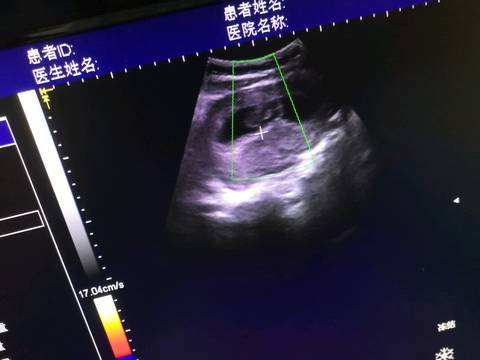

31周多|开始用胎心监护检测宝宝安全了

本周的产检项目包括血压、体重、宫底高度、腹围、胎心率、胎位、血常规、尿常规等。另外,有的医院会从32周...